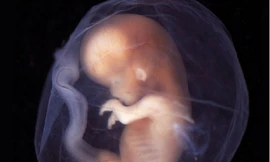

TPO - Ngày 28/5, một dấu mốc y khoa đặc biệt đã được ghi nhận tại TP.HCM khi các bác sĩ Bệnh viện Từ Dũ và Bệnh viện Nhi đồng 1 phối hợp thực hiện thành công ca can thiệp tim bào thai thứ 9 – ca bệnh cực kỳ phức tạp cho một thai phụ quốc tịch Singapore. Trước kỳ tích này, Bộ trưởng Bộ Y tế đã gửi thư khen, biểu dương tinh thần vượt khó, trình độ chuyên môn và y đức cao cả của đội ngũ thầy thuốc Việt Nam.

TPO - Dị tật tim bẩm sinh hiếm gặp – không lỗ van động mạch chủ - có tỷ lệ tử vong rất cao nếu không được can thiệp kịp thời. Bệnh viện Singapore đã chủ động giới thiệu sản phụ sang điều trị tại Bệnh viện Từ Dũ và Nhi Đồng 1 TPHCM.

TPO - Liên tiếp 2 ca thông tim xuyên tử cung, cứu sống thai nhi bị dị tật tim nặng ngay khi còn trong bụng mẹ đã được Bệnh viện Từ Dũ phối hợp cùng Bệnh viện Nhi Đồng 1 thực hiện thành công. Kỹ thuật này vừa được trao giải thưởng Thành tựu Y khoa Việt Nam tối 26/2.

TPO - Ngày 30/1, Bệnh viện Từ Dũ TPHCM cho biết, cháu bé được thực hiện thành công ca thông tim xuyên tử cung đầu tiên tại Việt Nam đã chào đời khỏe mạnh với cân nặng 2,9kg.